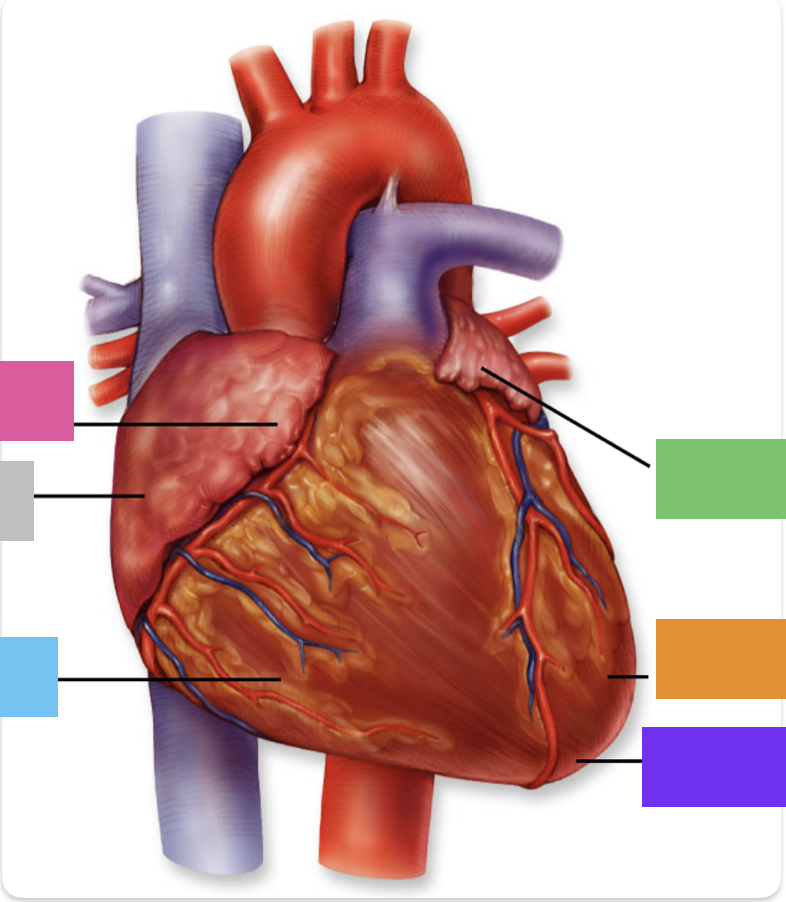

light purple

base

purple

apex

grey

right atrium

pink

right auricle

green

left atrium

green

left auricle

blue

right ventricle

orange

left ventricle

green

coronary (atrioventricular) sulcus

green

anterior interventricular sulcus

red

right coronary artery

yellow

posterior interventricular artery

green

left coronary artery

blue

anterior interventricular artery

pink

circumflex artery